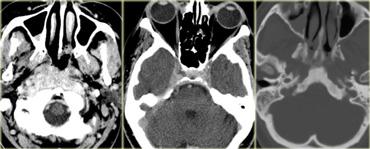

Hình bên trái là CT không tiêm và CT có tiêm thuốc cản quang của bệnh nhân nữ 33 tuổi với biểu hiện đau đầu dữ dội (nặng hơn vào buổi sáng), giảm thị lực và thu hẹp thị trường, kèm phù gai thị.

Tiếp tục xem hình ảnh MRI.

Lưu ý tuyến yên bình thường bị đẩy xuống dưới.

Điều này cho thấy đây không phải là u tuyến yên đại thể (macroadenoma).

Chẩn đoán một lần nữa là u sọ hầu (craniopharyngioma).

Chẩn đoán phân biệt bao gồm u tế bào hình sao (astrocytoma) và u màng não (meningioma).